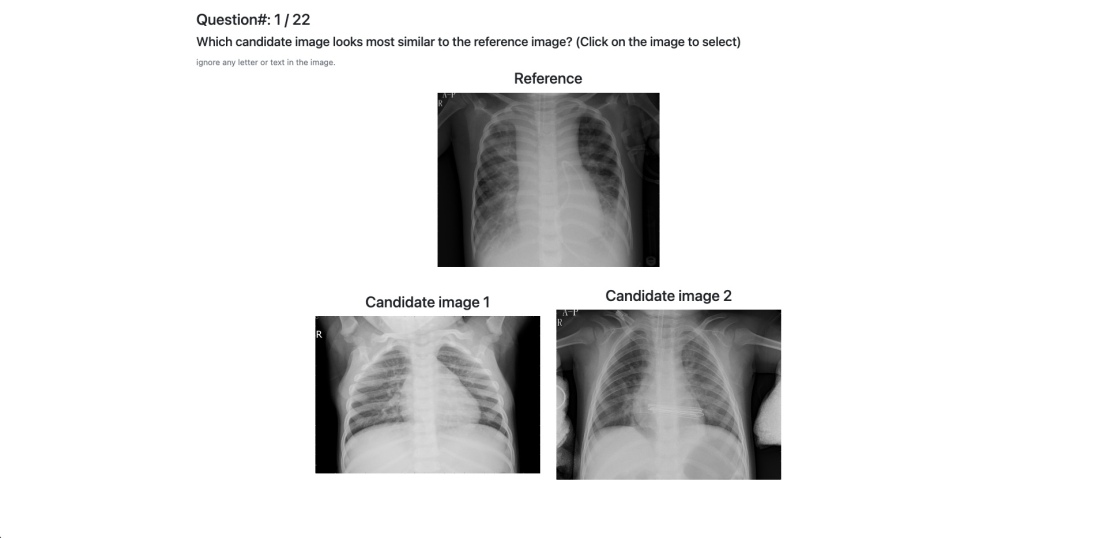

5.1 Triplet annotation

We recruit crowdworkers on Prolific to acquire visual similarity triplets. In each question, we show a reference image on top and two candidate images below, and ask a 2-Alternative-Forced-Choice (2AFC) question: which candidate image looks more similar to the reference image? A screenshot of the interface can be found in the appendix. To generate triplets for annotation, we first sample the reference image from either the training, the validation, or the test set. Then for each reference image, we sample two candidates from the training set. We sample the candidates only from the training set because in decision support, the selected examples should always come from the training set, and thus we only need to validate and test triplet accuracies with candidates from the training set.

For BM we recruit 80 crowdworkers, each completing 50 questions, giving us 4000 triplets. For CXR we recruit 100 crowdworkers, each answering 20 questions, yielding 2000 triplets. Our pilot study suggests that visual similarity judgment on chest X-rays is a more mentally demanding task, so we decrease the number of questions for each CXR survey.